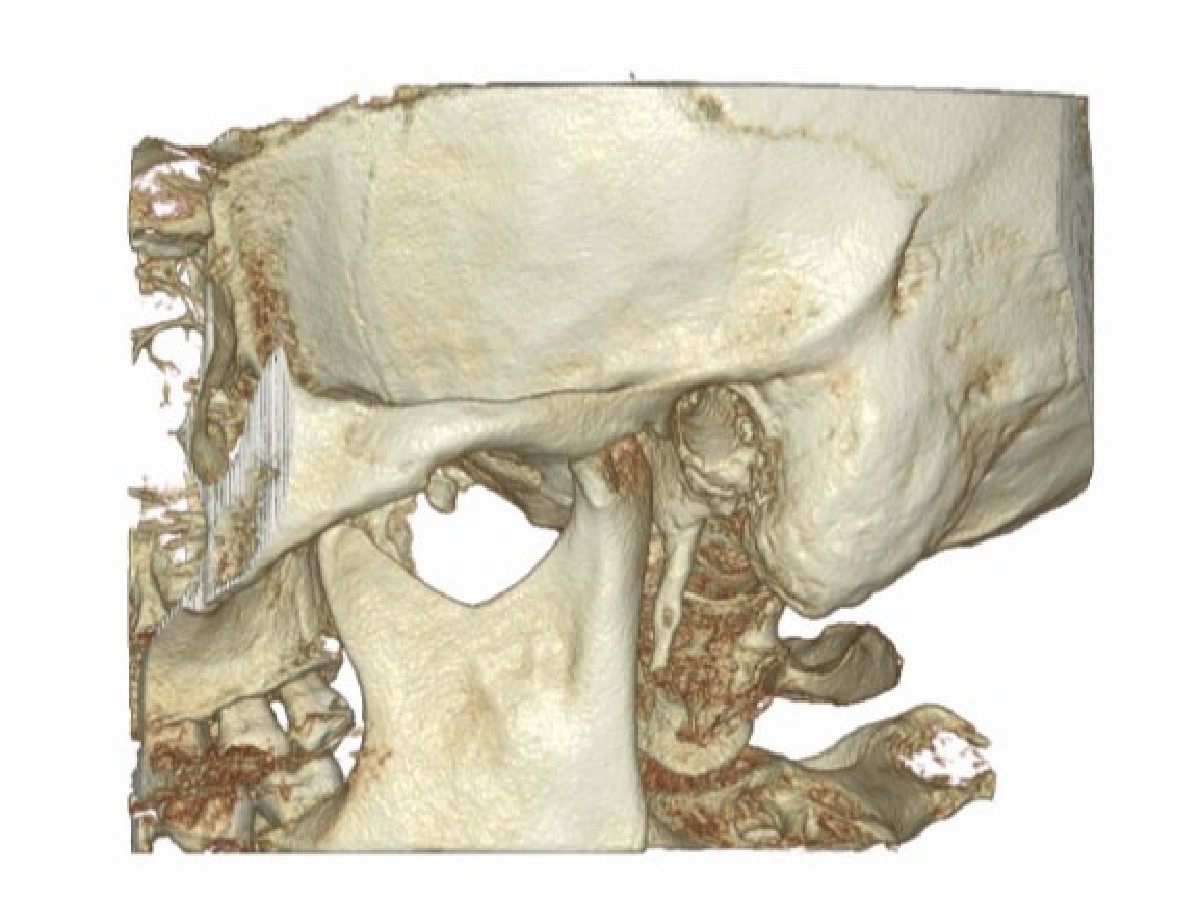

Tomografia ucha jest badaniem, podczas którego wykorzystuje się promienie rentgenowskie do uzyskania precyzyjnych, warstwowych skanów struktur ucha środkowego i wewnętrznego. Dzięki wysokiej rozdzielczości pozwala na wykrycie zmian, takich jak otoskleroza, przewlekłe stany zapalne, wady wrodzone, urazy czy nowotwory. Badanie jest bezbolesne i trwa zaledwie kilka minut. W ESDENT do jego przeprowadzania wykorzystujemy tomografy CBCT, emitujące najniższą, bezpieczną dawkę promieniowania.

Podczas RTG ucha pacjent ustawia się przed urządzeniem, a jego głowa zostaje ustabilizowana, aby uniknąć poruszeń. Tomograf wykonuje serię precyzyjnych skanów w kilku płaszczyznach, tworząc szczegółowy obraz struktur kostnych ucha. Cała procedura trwa kilkanaście sekund – podczas niej należy pozostać nieruchomym. W niektórych przypadkach stosuje się środek kontrastowy dla lepszej wizualizacji tkanek. Po zakończeniu badania specjalista analizuje obrazy i przekazuje wyniki wraz z opisem.

Tomografia CBCT pozwala na precyzyjną ocenę struktur kostnych i wykrycie nawet drobnych zmian, co ma kluczowe znaczenie dla planowania leczenia i minimalizacji ryzyka powikłań. Jest ona wskazana w przypadku podejrzenia otosklerozy, wad wrodzonych, przewlekłych stanów zapalnych, urazów czy zmian nowotworowych. To badanie niezbędne przed zabiegami rekonstrukcji kosteczek słuchowych, tympanoplastyką, mastoidektomią oraz implantacją ślimakową. Wykonuje się je także w diagnostyce nagłej utraty słuchu, zawrotów głowy oraz niejasnych dolegliwości bólowych.